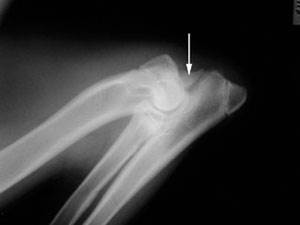

Клинический осмотр может определить, является ли локтевой сустав отечным или болезненным, несмотря на то, что первоначально хромоту может быть трудно локализовать. Подтверждение диагноза дисплазии локтевого сустава производится путем выполнения дальнейших исследований (КТ или рентгенографии).

С помощью рентгена можно определить, есть ли собаки дисплазия локтевого сустава. Делается это путем идентификации основной проблемы или остеоартрита, появляющегося в результате. Три кости (плечевая кость, лучевая и локтевая кость) объединяются для формирования локтевого сустава, и они накладываются на рентгенограммах. Это делает идентификацию основного поражения проблематичной в некоторых случаях.